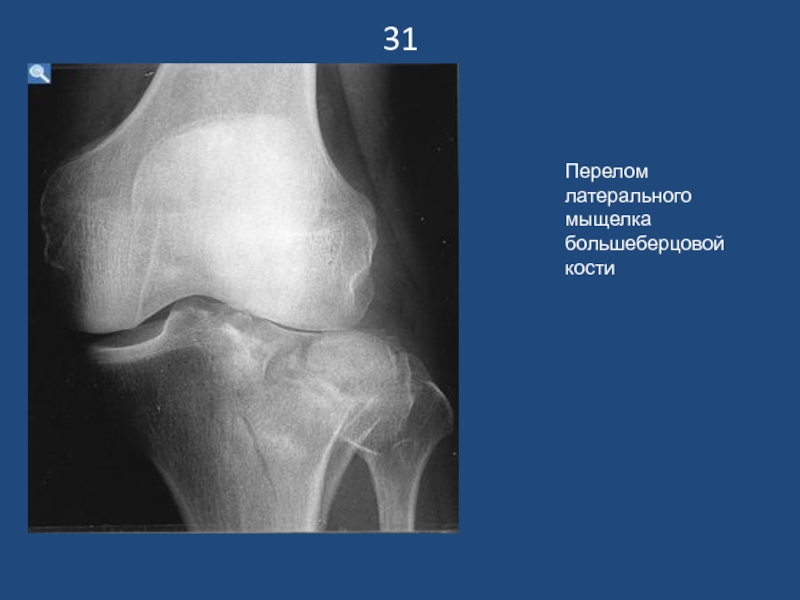

Слайд 3231

Перелом латерального мыщелка большеберцовой кости

31Перелом латерального мыщелка большеберцовой кости